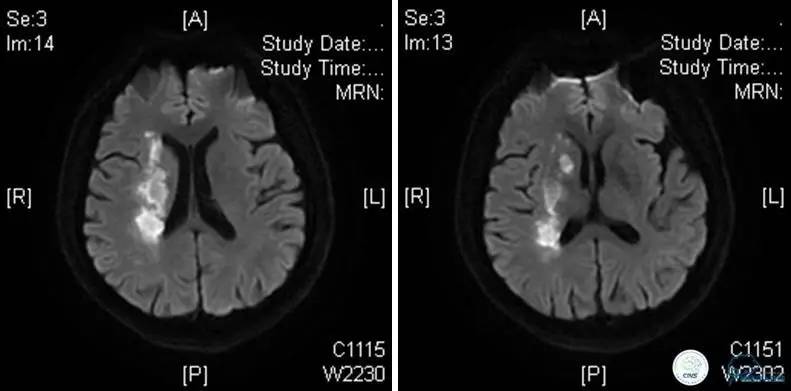

患者:49岁男性,左侧偏瘫1个月,药物治疗、康复训练效果不好,转我院,肌力0~1级。

core-clilnical明显不匹配,是介入开通的合适患者。

造影评价血管、判断闭塞段,微导丝小心穿过闭塞段,微导管造影,交换技术,球囊扩张,Enterprise支架。在后扩张时导丝刺破M3段血管,蛛网膜下腔出血(SAH)。

微导管进入破裂血管,栓塞弹簧圈1枚,出血停止,结束手术。继续双抗,术后2天肌力2级,神经功能恢复明显加快。

术后即刻和6天后CT,患者无明显临床症状。

半年后复查造影,无支架内再狭窄,可见弹簧圈,患者恢复至自己柱杖行走。